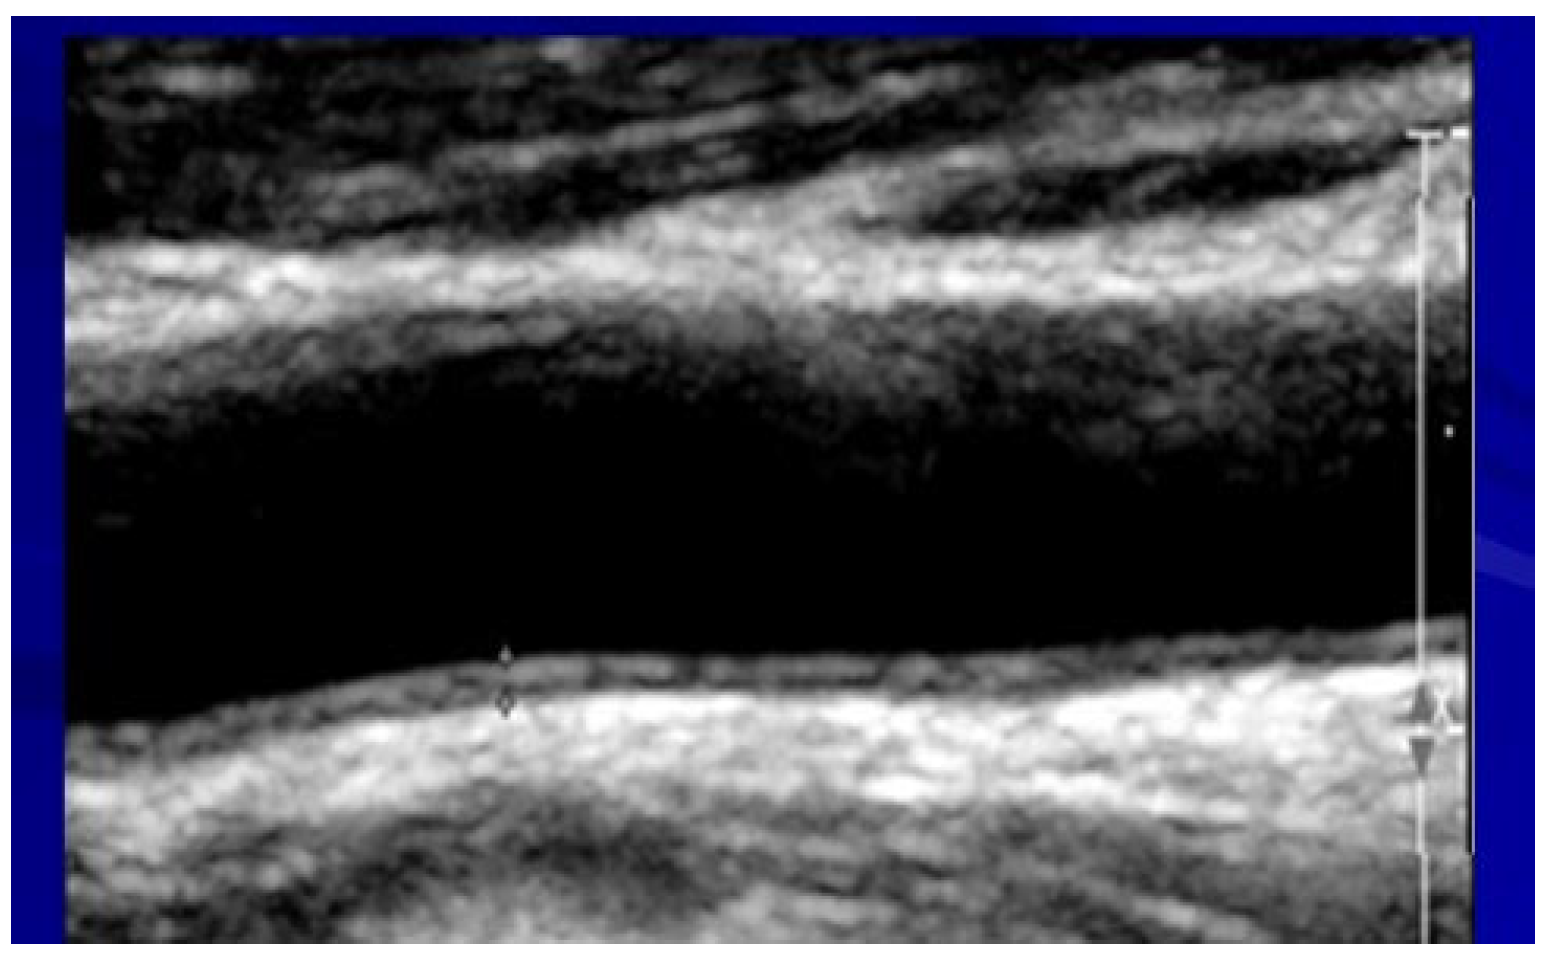

2.5. Assessment of Carotid Atherosclerosis

All patients underwent carotid ultrasounds for intima–media thickness (IMT) evaluation and plaques. A high-resolution ultrasound device (Sonos 5500; Agilent Technologies, Palo Alto, CA, USA) and a 10 MHz linear array transducer were used for carotid scans. Longitudinal views of the following were obtained: the left and right common carotids, carotid bifurcations, and internal and external carotid arteries. All ultrasound studies (carotid and brachial flow-mediated dilation) were analyzed off-line using the Prosound system by specially trained technicians who were blinded to other study variables. IMT was measured over 10 mm in the far wall of the common carotid within 2 cm proximal to the bulb (Figure 3).

Figure 3.

An ultrasound image of the carotid artery for evaluating intima–media thickness.

The thickest IMT region without focal lesions was measured. Both right and left carotids’ IMT values were averaged. The intima–media area was defined as previously described [24]:

Intima–media area in mm2 = (IMT mm) × (length over which IMT was measured in mm).

Plaques were quantified for all the carotid segments (common, internal, and external carotid arteries). Normal ranges were <7 mm for males and <0.65 for females.